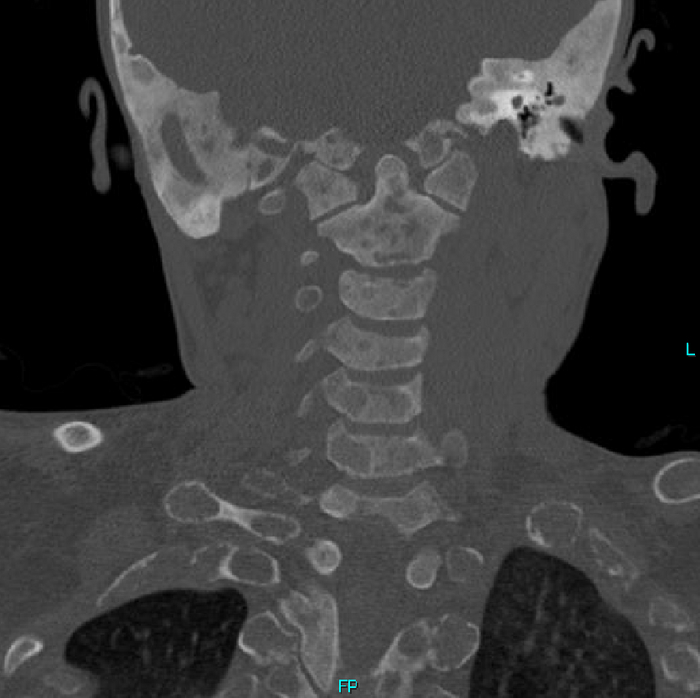

Но вернёмся к случаю: Пациент - девочка, 15 лет. Поступила после ДТП. У нас было проведено КТ-обследование по протоколу политравмы (голова / шея / грудь / живот / таз), где свежих переломов обнаружено не было, но были непонятные леденцы с костями, а именно структура и форма костей со следами старых переломов (грудная клетка и таз с бедренными костями) и, как следствие, их деформацией + следы проведённого остеосинтеза (операция с последующей фиксацией кости тем или иным способом) обоих бедренных костей. Сегодня без пометок / стрелочек, так как картинки говорят сами за себя (всё в костном окне, и всё, что мы видим - кости):

Структура костей напоминала таковую при фиброзной дисплазии (аномалия развития костной ткани с замещением нормальной кости фиброзной тканью, не является опухолью), но, обычно, эти диcплазии возникают в одном месте, т.е. поражают 1 кость (моностотическая форма) и, намного реже, бывают множественные поражения (полистотическая форма), но не всего скелета, как в нашем случае.